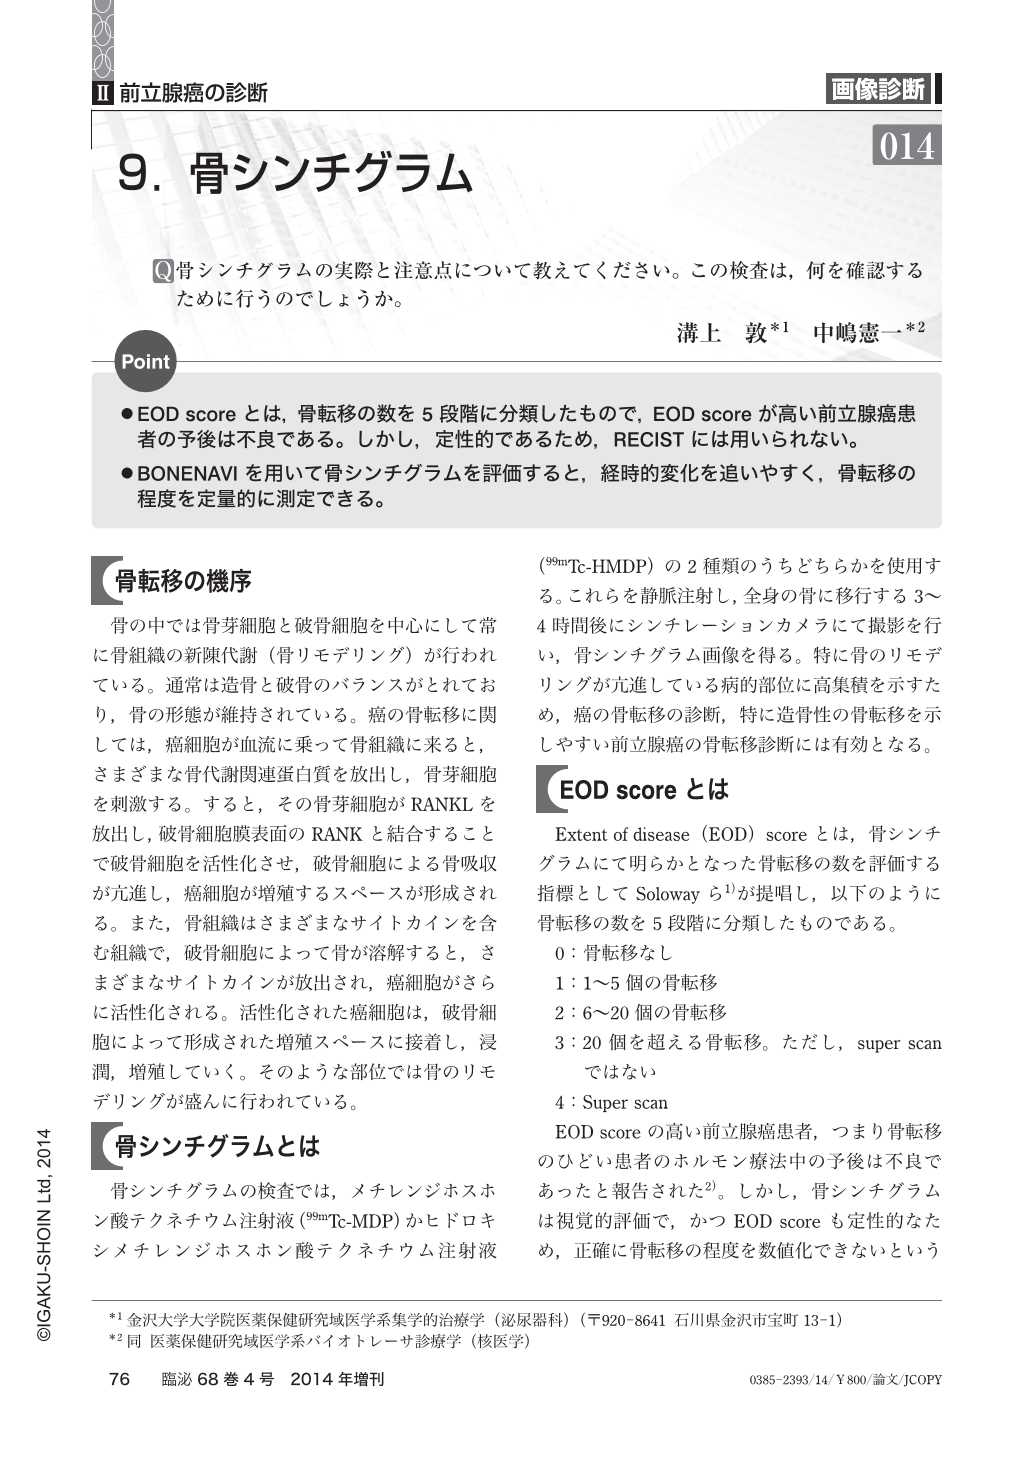

全身骨シンチグラフィ 乳癌 肺癌 前立腺癌等の骨転移病巣の検出

全身骨シンチグラフィ 乳癌 肺癌 前立腺癌等の骨転移病巣の検出

骨シンチグラフィによる骨転移の診断 Bone Scan Ct Mri画像診断